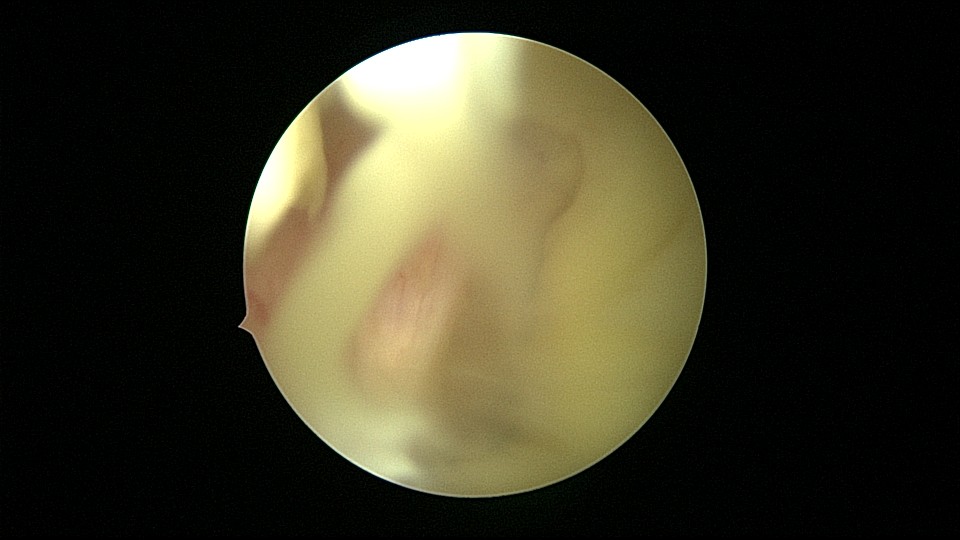

54岁,G2P1,顺产1次,安环16年,绝经10年,无不适症状,B超提示节育器嵌顿,宫腔积液2.3cm*1.9cm,血常规正常,白带常规乳酸杆菌少,其余指标正常。宫腔镜见宫颈管中上段封闭粘连,镜鞘分离粘连,见V型环一臂铜环全部嵌入右侧宫壁肌层内,取出节育器,宫腔内见灰白色脓液漂浮,膨宫液冲洗脓液,宫腔镜下无脓苔后结束手术,术后抗炎治疗。病检:宫腔少许宫内膜,呈慢性炎改变。